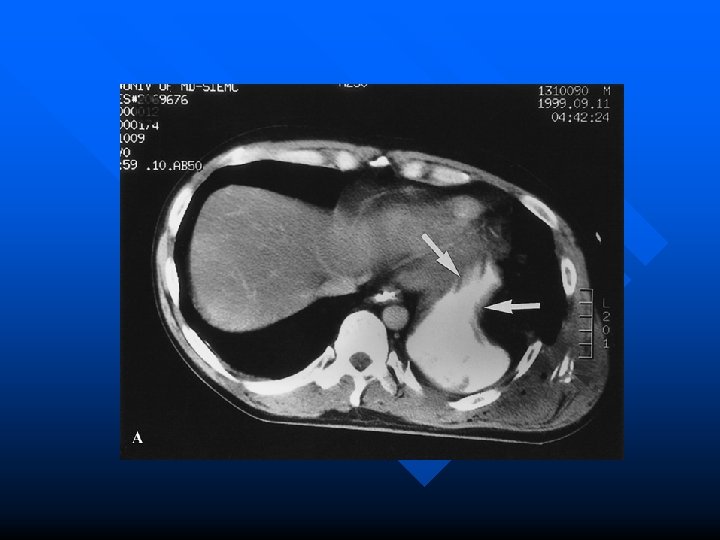

Chest CT n Many advantages over aortography – readily accessible in most urban ED’s – low complication rate – less contrast – fast – gives information about structures other than the aorta

Evidence for CT in Blunt Trauma? n Early scanners (non-helical) were disappointing but new helical CT’s have sensitivities of 100% and specificity of 96 % Mirvis et al. Traumatic aortic injury. Diagnosis with contrast enhanced thoracic CT—five year experience at a major trauma center. Radiology 1990; 176: 181 -183 Garrant et al. Blunt traumatic aortic rupture. Detection with helical CT of the chest. Radiology 1995; 197: 125 -133. n Demetriades et al. concluded that “all trauma patients with high risk deceleration injuries undergo routine helical CT irrespective of CXR findings” Demetriades et al. Routine helical CT evaluation of the mediastinum in the high risk trauma patient. Arch Surg 1998; 133: 1084 -1088.

Helical CT in Penetrating Trauma n In stable patients with a GSW to the torso, CT can be used to follow the trajectory of the bullet thereby decreasing the need for exploratory surgery Grossman et al. Determining anatomical injury in selected torso gunshot wounds. J Trauma 1998; 446 -456